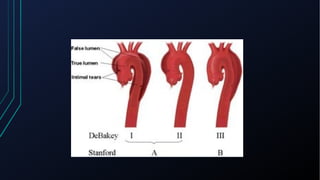

Dor torácica pode ter diversas causas, incluindo cardíacas como síndrome coronariana aguda, dissecção de aorta e pericardite, e não cardíacas como problemas pulmonares, musculoesqueléticos e do trato gastrointestinal. É importante avaliar a história clínica, características da dor e exame físico para identificar a possível causa e orientar o tratamento adequado.